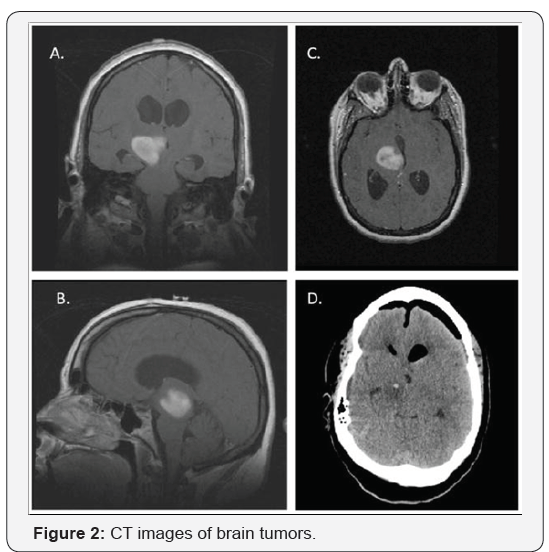

Glioblastoma (GB), also known as Glioblastoma Multiform (GBM), is the most common primary brain tumor in adults. It remains an unmet need in oncology. The survival rate is ~1 year, and only 5% of the people affected live for 5 years. Figure 1 is an illustration of the appearance of GBM while Figure 2 contrasts an actual GBM with the corresponding contrastenhanced CT images. In a recent review article [1], the various treatment modalities devised so far for primary and recurring GBMs after treatment and their metastases, have been described in detail. These included surgery, conformal radiotherapy, boron neutron therapy, intensity modulated proton beam therapy, Antiangiogenic therapy, alternating electric field therapy, micro RNA, immunotherapy, adjuvant therapy, gene therapy, stem cell therapy and intranasal drug delivery without neglecting palliative therapies. Unfortunately, to date, the trials have not shown a benefit in overall survival (OS) either in the case of Antiangiogenic agents alone or in combination with chemo radiotherapy.